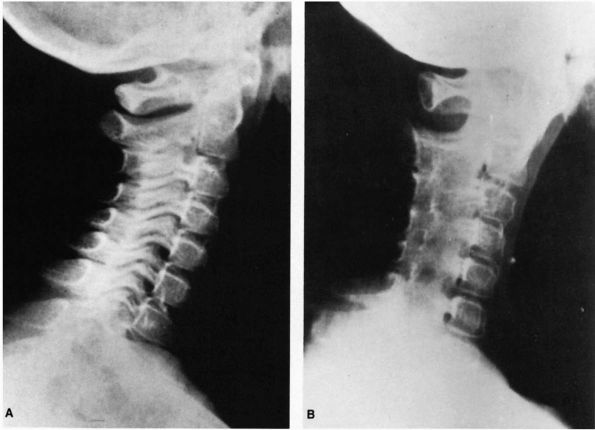

FIGURE 11-1.

Torticollis is head tilt with rotation. Congenital muscular torticollis and rotatory subluxation of the atlas on the axis are the two most common causes in children. Facial asymmetry is present. |